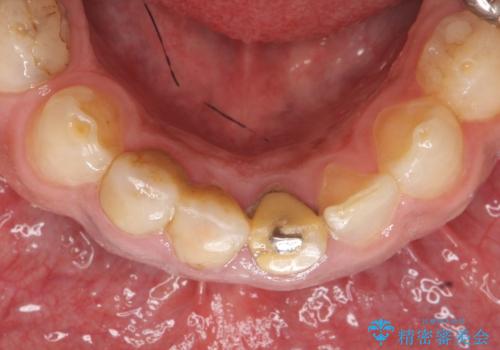

- 歯がない左側でものが咬めず、右側で咬むと歯が痛むので診て欲しいといらっしゃった方の症例です。

根尖病変が認められる歯は再根管治療を行い、歯根が破折していた左上4は抜歯しました。

インプラントは希望されなかったため、左側は1番から7番のロングスパンブリッジによる補綴を行いました。